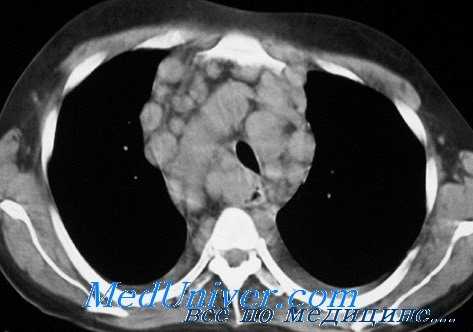

К КТ-признакам экстранодальных поражений при лимфомах относятся: очаговые образования, перибронхиальная инфильтрация, увеличение лимфатических узлов средостения, гидроторакс, поражение тканей грудной клетки.

Очаговые образования в легких выявляются в виде множественных субплевральных очагов лимфоидной ткани однородной плотности диаметром около 1 см. Очаги больших размеров неправильной формы встречаются редко.

Перибронхиальная и/или перивазальная инфильтрация наиболее выражена в периферических отделах легких и всегда имеет связь с плеврой. Она же обусловливает гиповентиляцию, иногда приводящую к ателектазам.

Поражения лимфатических узлов при лимфогранулематозе (ЛГМ) и неходжкинских лимфомах (НХЛ) различаются. При ЛГМ поражаются преимущественно ретростернальная, перикардиальная, трахеобронхиальная и бронхопульмональная группы; форма поражения — изолированная, пакет, реже инфильтрат. При НХЛ эти группы поражаются менее чем в 15% случаев; форма поражения изолированная, реже в виде пакета и конгломерата.

В плевральной полости на стороне поражения может определяться гидроторакс, обычно односторонний и незначительно выраженный.

Из субплевральных очагов и образований средостения лимфоидная ткань распространяется на ткани грудной стенки; иногда в процесс вовлекаются органы средостения, плевральная полость, легкие. Это более характерно для НХЛ.

КТ органов грудной клетки при болезни Ходжкина

Поражение перикарда определяется в виде утолщения сердечной сумки до 5 мм и более, перикардиальный жир не прослеживается из-за перикардиальной лимфоидной инфильтрации, в полости перикарда имеется небольшое количество жидкости.